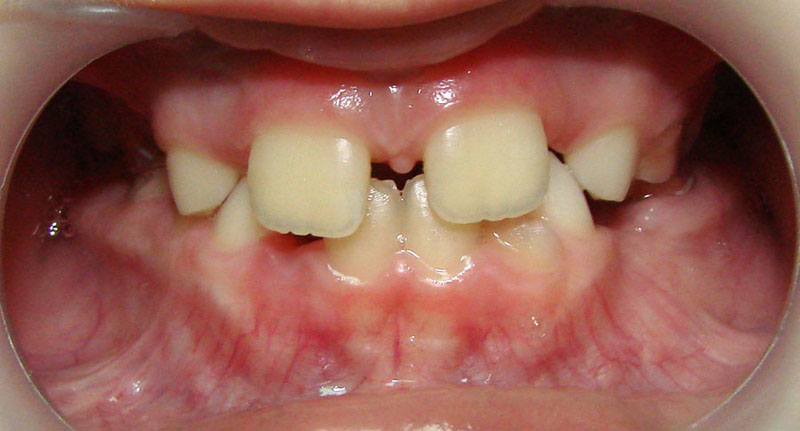

Покажу клинические случаи, чтобы было проще представить возможности ортодонтического лечения.

Начну с самого простого. Мальчик, 6 лет. Носил съемную плстинку 4 мес. В таком возрасте брекеты еще, как правило, не используют.